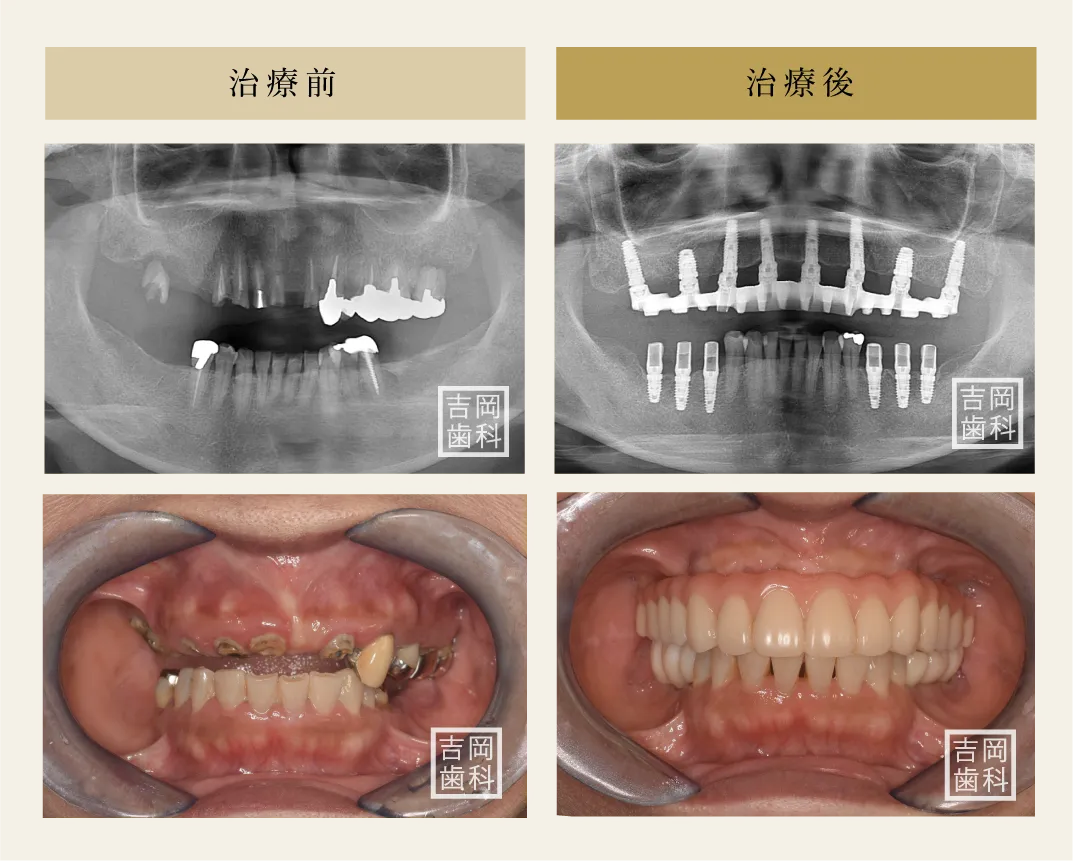

治療前

治療後